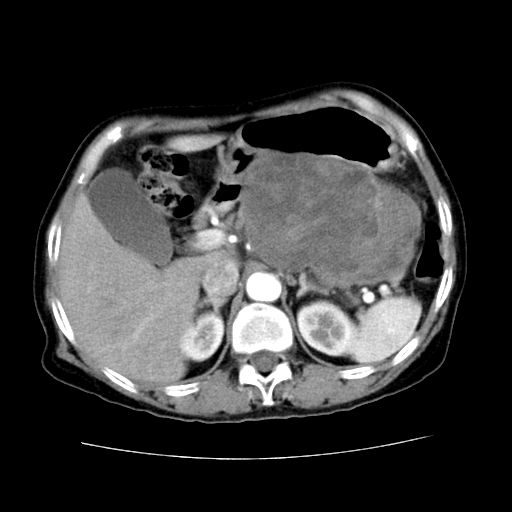

女性,72岁。

主诉中上腹部疼痛不适1年余。

胰腺尾部不规则巨大略低密度肿块,界限清楚,内密度不均,增强动脉期不均匀强化,门脉期明显退减并低于胰腺密度,肿瘤包埋于脾血管。多考虑;来源于胰腺尾部的“胰腺癌”。

1、这个病例确实有点难。影像主要显示胰腺体尾部占位,我们当初也是诊断胰体尾部囊腺癌可能性大,而且读片会上也很多人这么诊断的。

2、手术所见:打开腹腔发现胃与胰腺体尾部可见肿块,大小约10×8×11cm,质硬,不可推动,周围血供丰富。术中诊断:胃肿瘤侵及胰腺体尾部。

1)、胃小弯侧胃肠间质瘤(考虑恶性),瘤体大小13.5×7×6.5cm,上下切缘阴性。

2)、胃小弯1只、幽门下2只淋巴结慢性炎。免疫组化:cd117(+)、cd34(+)、sma(+)、desmin(-)、s-100(-)、ki-67<10%(+).

4、这个肿瘤太大了,而且密度不均性强化,从这点我们应该不能单纯诊断胰腺癌,而应想到目前流行的胃肠道间质瘤。这个肿瘤主要发生于胃壁浆膜层,所以显示与胃壁关系不是很紧密,故而大多认为是胰腺癌。